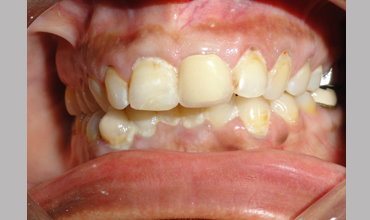

Management Of Fractured Central Incisor With Biological Post